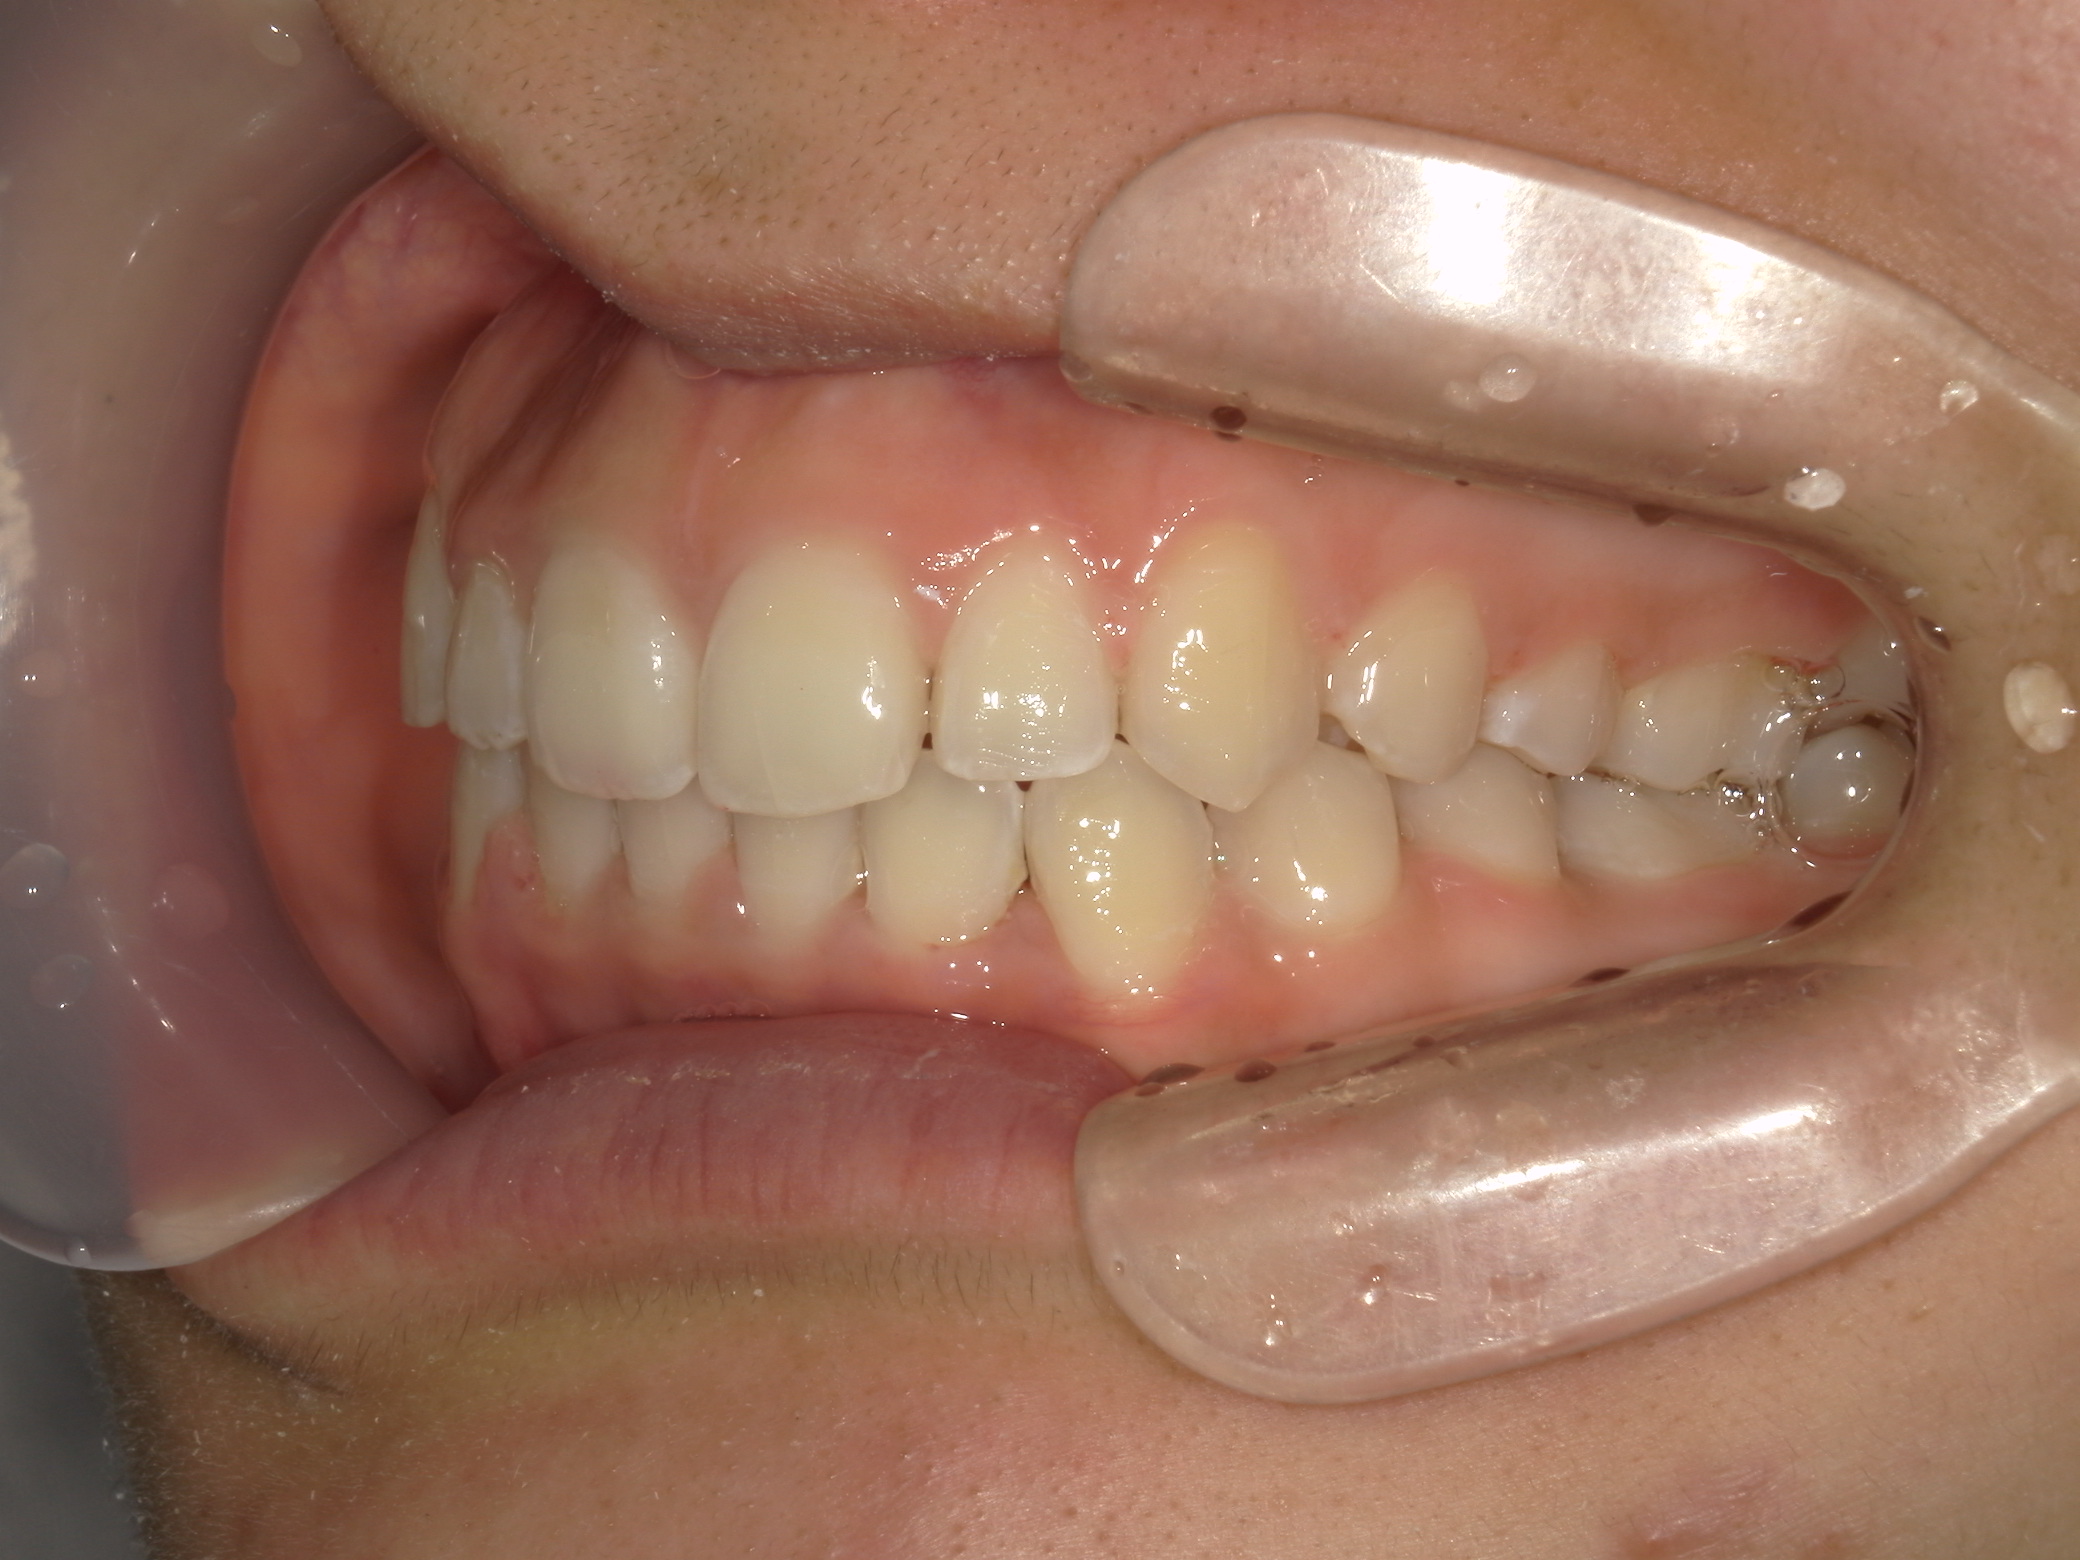

プチワイヤー矯正 症例(54)

主訴: 歯並びが気になる。

カテゴリー : ガタガタ(叢生)